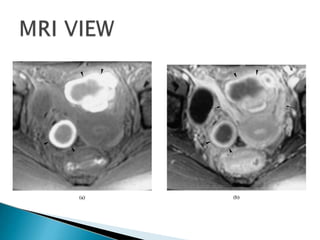

MRI –useful

Investigations Laparoscopy: Gold standardIt should not be performed within 3 months of hormonal treatment to prevent under diagnosis Ultrasound: Ultrasound has a limited role, however the addition of colour doppler claims to increase the sensitivity to 91.8%, specificity of 91.3% MRI –useful Ca 125-Maybe elevated in severe